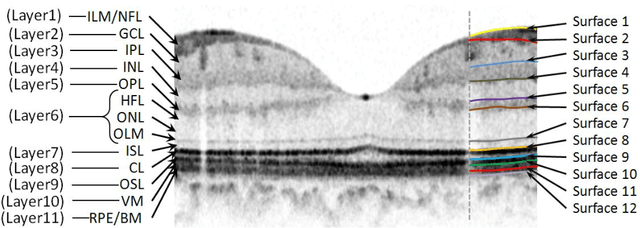

Abstract:Purpose. This study was conducted to determine the thickness map of eleven retinal layers in normal subjects by spectral domain optical coherence tomography (SD-OCT) and evaluate their association with sex and age. Methods. Mean regional retinal thickness of 11 retinal layers were obtained by automatic three-dimensional diffusion-map-based method in 112 normal eyes of 76 Iranian subjects. Results. The thickness map of central foveal area in layer 1, 3, and 4 displayed the minimum thickness (P<0.005 for all). Maximum thickness was observed in nasal to the fovea of layer 1 (P<0.001) and in a circular pattern in the parafoveal retinal area of layers 2, 3 and 4 and in central foveal area of layer 6 (P<0.001). Temporal and inferior quadrants of the total retinal thickness and most of other quadrants of layer 1 were significantly greater in the men than in the women. Surrounding eight sectors of total retinal thickness and a limited number of sectors in layer 1 and 4 significantly correlated with age. Conclusion. SD-OCT demonstrated the three-dimensional thickness distribution of retinal layers in normal eyes. Thickness of layers varied with sex and age and in different sectors. These variables should be considered while evaluating macular thickness.

Abstract:Optical coherence tomography (OCT) is a powerful and noninvasive method for retinal imaging. In this paper, we introduce a fast segmentation method based on a new variant of spectral graph theory named diffusion maps. The research is performed on spectral domain (SD) OCT images depicting macular and optic nerve head appearance. The presented approach does not require edge-based image information and relies on regional image texture. Consequently, the proposed method demonstrates robustness in situations of low image contrast or poor layer-to-layer image gradients. Diffusion mapping is applied to 2D and 3D OCT datasets composed of two steps, one for partitioning the data into important and less important sections, and another one for localization of internal layers.In the first step, the pixels/voxels are grouped in rectangular/cubic sets to form a graph node.The weights of a graph are calculated based on geometric distances between pixels/voxels and differences of their mean intensity.The first diffusion map clusters the data into three parts, the second of which is the area of interest. The other two sections are eliminated from the remaining calculations. In the second step, the remaining area is subjected to another diffusion map assessment and the internal layers are localized based on their textural similarities.The proposed method was tested on 23 datasets from two patient groups (glaucoma and normals). The mean unsigned border positioning errors(mean - SD) was 8.52 - 3.13 and 7.56 - 2.95 micrometer for the 2D and 3D methods, respectively.